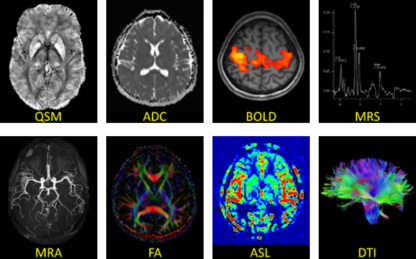

多模态磁共振影像分析

我们提供多模态磁共振数据分析服务包括但不限于:定量成像、功能成像、灌注成像、弥散成像以及分子成像等。